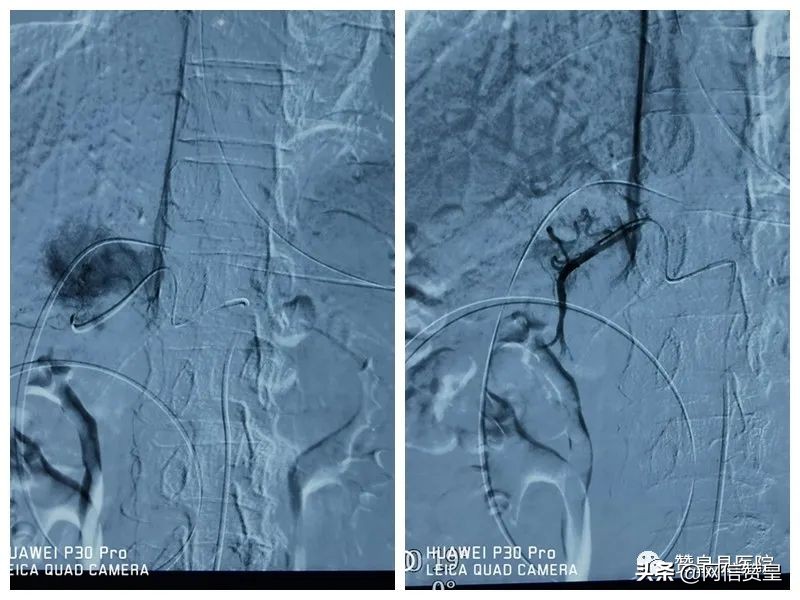

术后造影造影显示栓塞良好。